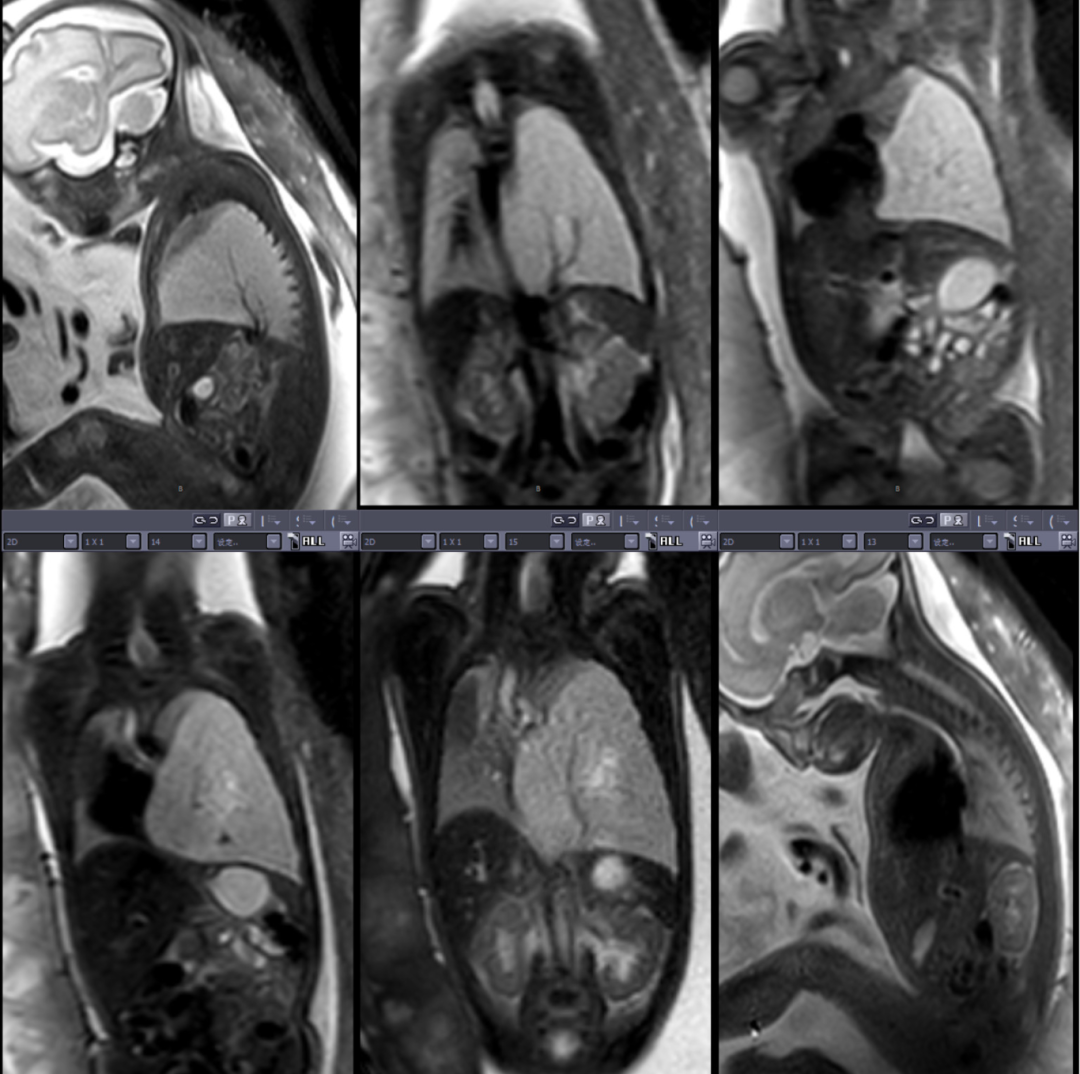

从孕23 周到36 周,产科胎儿医学及双胎诊治中心鲁云涯医生密切追踪,安排了7 次超声、2 次MRI 检查等富有成效的产前评估,并联合超声科、放射科动态监测胎儿胸部肿块的变化情况。

这份严谨的坚守至关重要。孕30周时肿块最大直径一度高达61mm ,CVR 值是评估肺部肿块风险的关键,正常情况下CVR>1.6提示高风险水肿,而此时胎儿的CVR已达到3.27。

新生儿科团队则需关注患儿出生后呼吸支持方案,提前备好呼吸机和 CPAP 设备。放射科陈凤英主任医师通过三维重建技术,清晰标注出肿块与心脏、大血管的位置关系,为手术规划提供 "导航图"。

出生后,胸部CT 再次明确诊断 "左侧巨大隔离肺"。在新生儿科专科主任刘卫东团队的精心呵护下,宝宝平稳度过了危险期:呼吸循环稳定、营养支持到位,有效控制感染。

长期以来,我院小儿外科积累了丰富的胎儿及新生儿手术经验,麻醉科对此类患儿的术中监护也经验十足,但面对患儿胸腔空间狭小,肿块紧邻心脏和大血管,稍有不慎就会引发致命出血等因素,外科副主任唐华建还是强调了手术挑战性:这台手术如同 "在刀尖上跳舞"—— 整个手术过程肿块都随着心脏跳动而摆动,既要完整切除肿块,又要精准结扎异常血管,还要避免损伤正常肺组织。

手术在胸腔镜下进行,3个0.5 cm的切口成为 "战场入口"。在高清内镜视野下,唐华建精准定位直径仅约3 毫米的异常供血血管,使用特制的微型钳夹成功结扎。分离肿块时,他像 "剥洋葱" 般逐层剥离粘连组织,动作轻、准、稳。

1小时 20 分钟后,长达6cm的肿块被完整切除,术中出血量控制至仅2ml。术后病理报告证实为"隔离肺"。